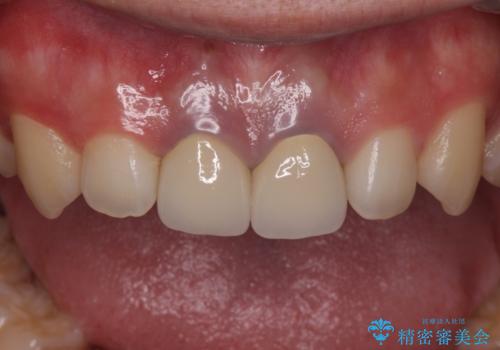

二本とも神経の治療のやり直し(再治療)を行ってからセラミックを入れています。

- 52.8万円 セラミッククラウン(メタルボンドクラウン11万円×2 仮歯1万円×2 ファイバーコア2万円×2 再根管治療9万円×2)費用は治療当時の料金となります

今回は、前歯のかみ合わせが深く、下の前歯が根元にかみこむような状態だったため、オールセラミックは難しく、メタルボンドクラウン(金属の裏打ちにセラミックが盛ってあるクラウン)となりました。

神経の治療をした歯は変色してくるため、歯ぐきから歯の根が透けて見えるのは治療はむずかしいです。